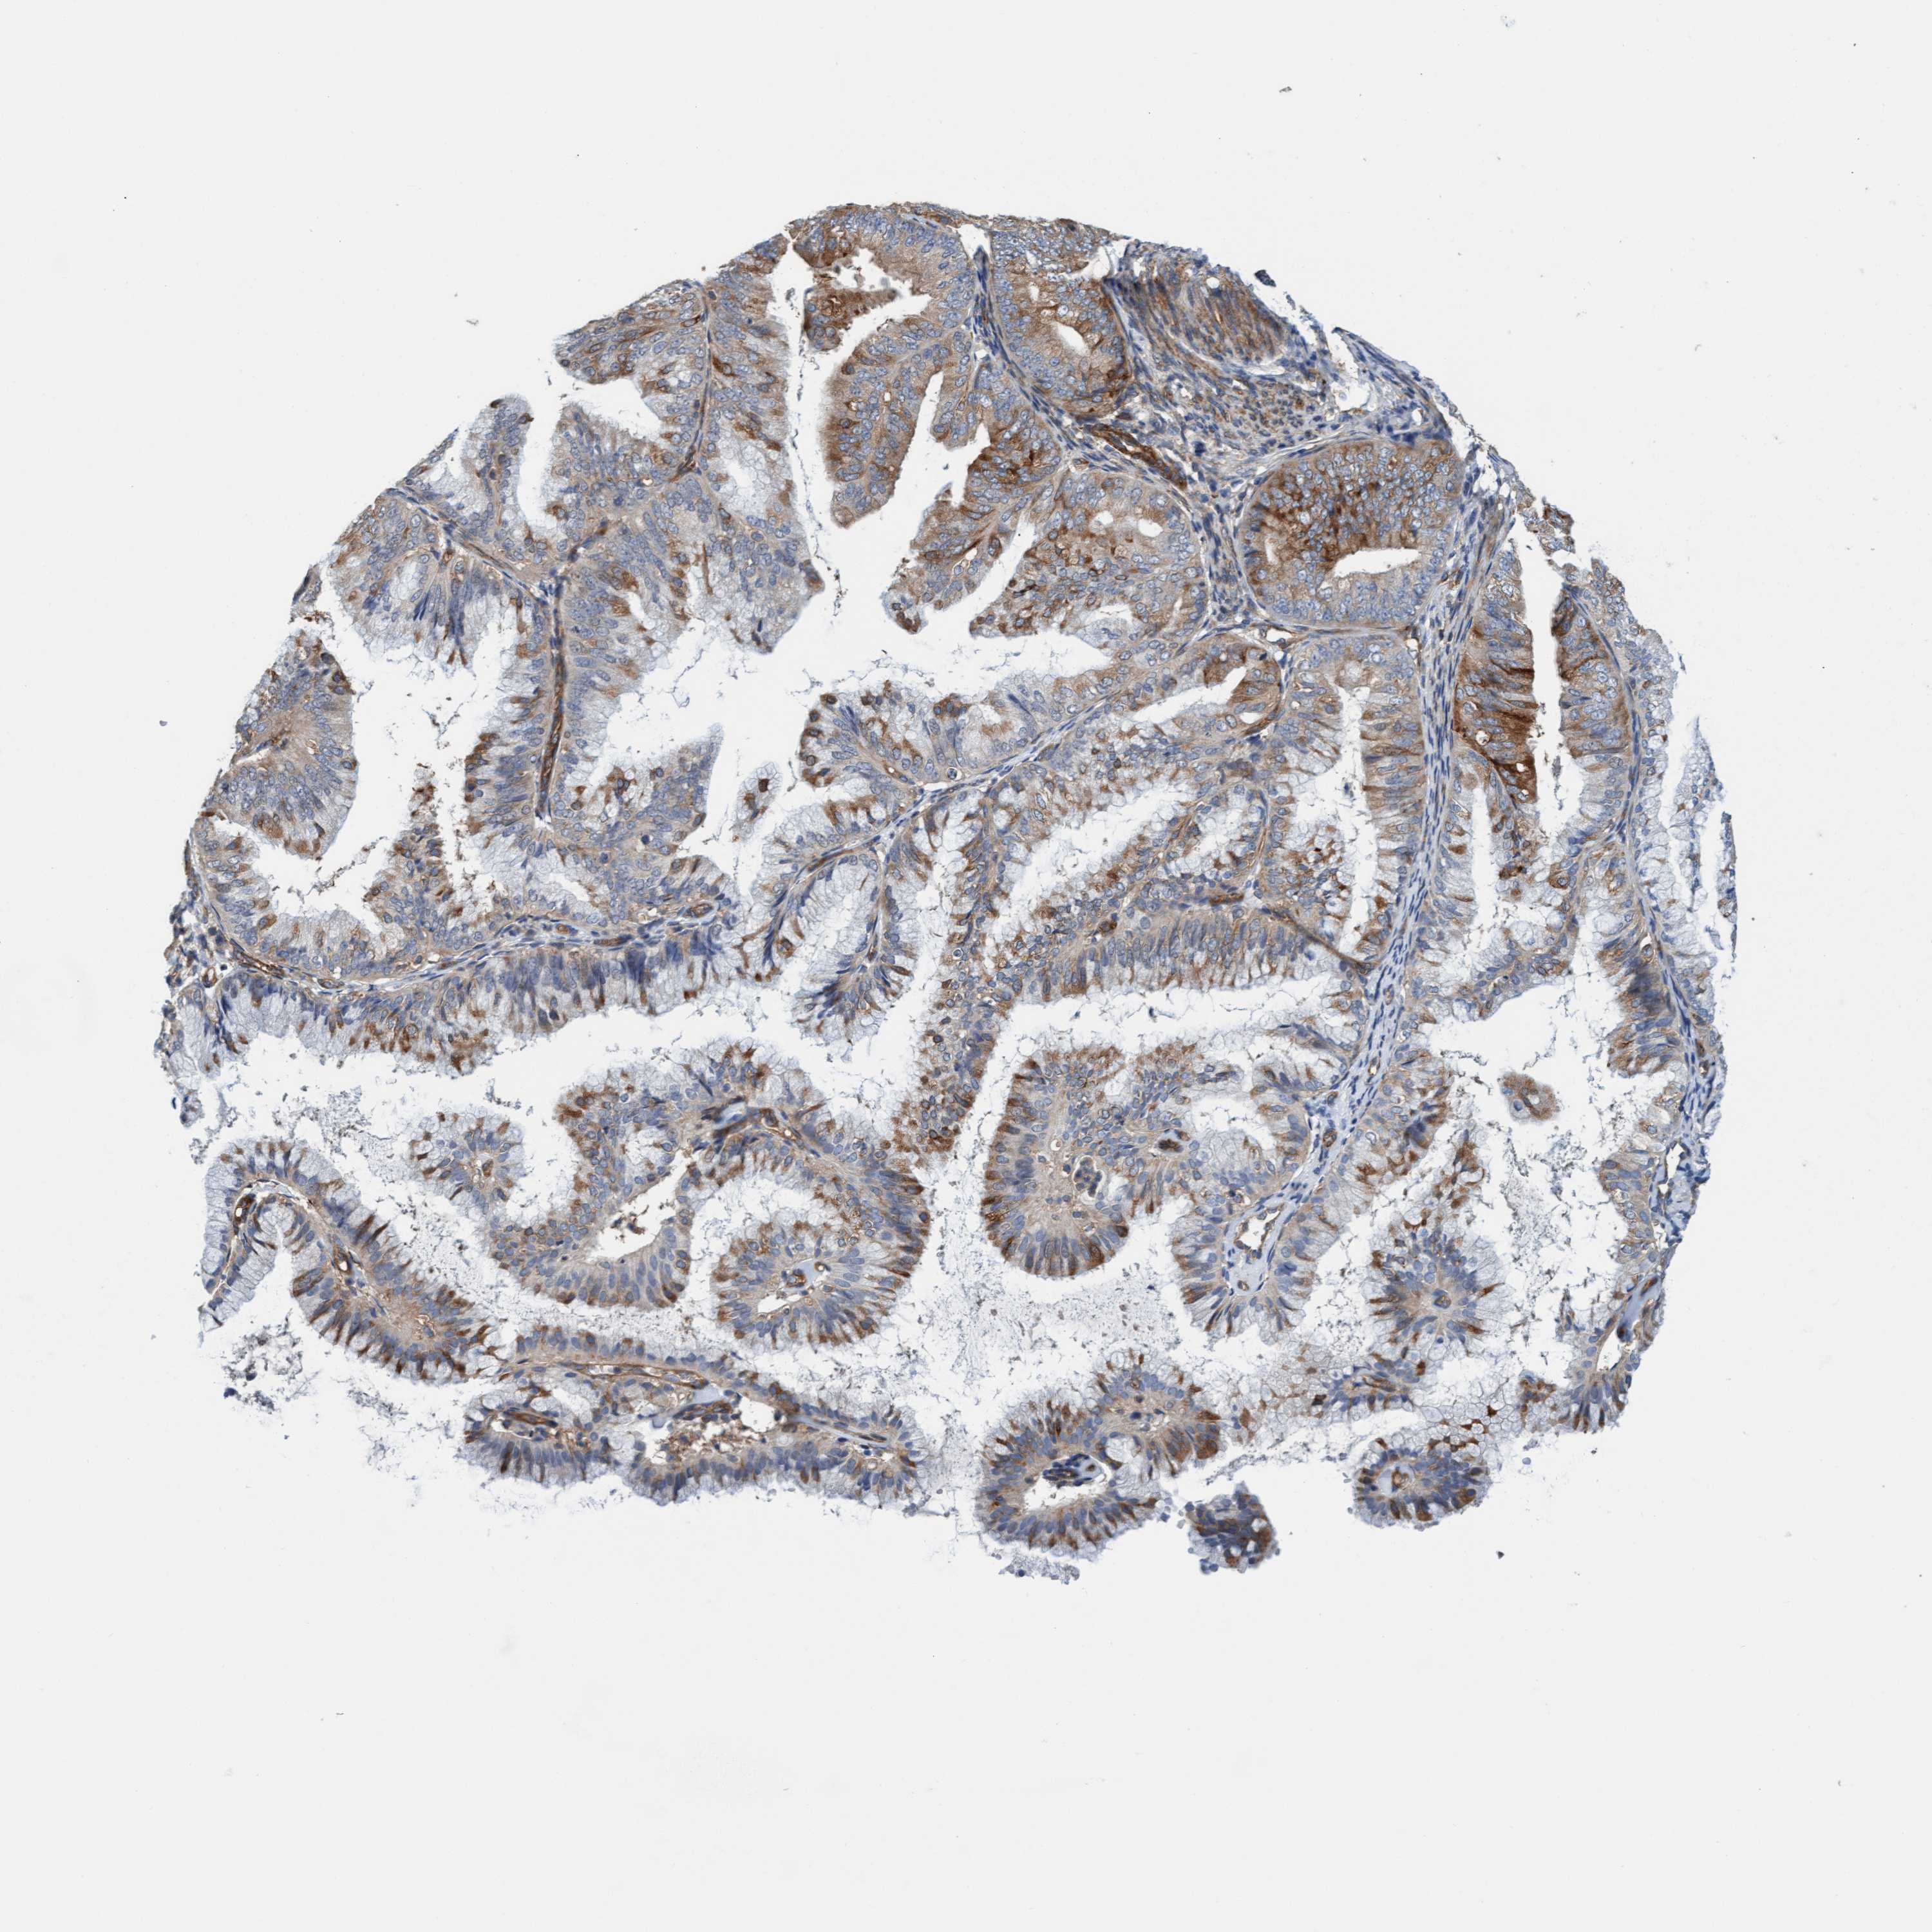

ENDOMETRIAL CANCER - Protein expressioni

A mouse-over function shows sample information and annotation data. Click on an image to view it in a full screen mode. Samples can be filtered based on level of antibody staining by selecting one or several of the following categories: high, medium, low and not detected. The assay and annotation is described here.

Note that samples used for immunohistochemistry by the Human Protein Atlas do not correspond to samples in the TCGA dataset.

Antibody stainingi

Antibody staining in the annotated cell types in the current human tissue is reported as not detected, low, medium, or high, based on conventional immunohistochemistry profiling in selected tissues. This score is based on the combination of the staining intensity and fraction of stained cells.

Each image is clickable and will lead to virtual microscopy that enables deeper exploration of all samples and also displays staining intensity scores, fraction scores and subcellular localization as well as patient and tissue information for each sample.

Antibody HPA002552

Antibody HPA023201

Staining

High

Medium

Low

Not detected

Intensity

Strong

Moderate

Weak

Negative

Quantity

>75%

75%-25%

<25%

None

Location

Nuclear

Cytoplasmic/membranous

Cytoplasmic/membranous,nuclear

Adenocarcinoma, NOS

Adenoma, NOS